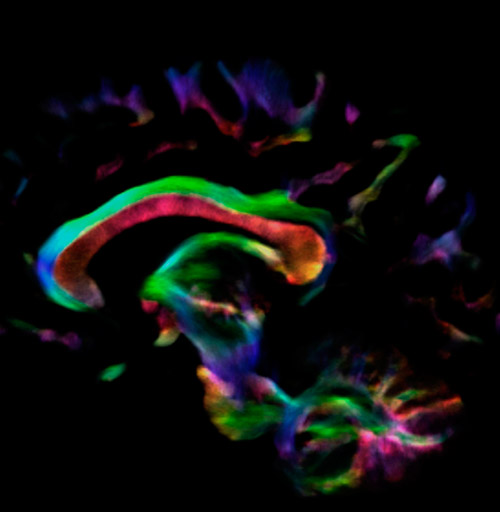

Fiber tractography of the corticospinal tract with seed region of the posterior limb of the internal capsule. Different processing based on the same data.

All images were created from the same acquisition in a child using Ingenia 3.0T CX and 32-channel dS Head coil. Diffusion data was acquired at b-values 0, 500, 1000, 2000, 3000. The use of high b-values (3000 s/mm2) effectively suppresses extra-axonal water signal and provides high angular resolution.

Fiber tracking from the left and right hippocampi to the fornix (green), and the corticospinal track based on a seed region of the posterior limb of the internal capsule.